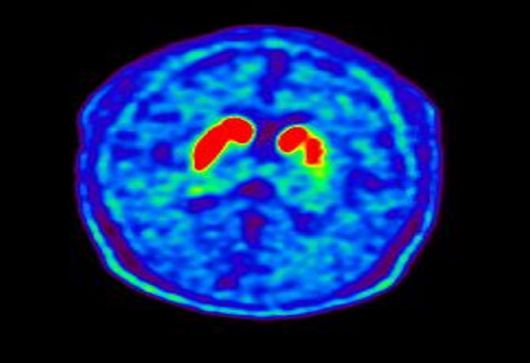

파킨슨병은 대표적인 퇴행성 뇌질환으로 신경전달물질인 도파민을 비롯한 다양한 뇌 신경세포가 사멸하여 떨림, 경직, 보행장애와 같은 운동 증상과 치매, 망상, 우울증, 자율신경장애, 수면장애 등의 비운동 증상을 보인다. 발병 원인은 정확히 규명되지 않았으나 최근 들어 유전적 요인과 더불어 살충제, 제초제, 금속, 기타 독성 물질 등 환경적 요인도 파킨슨병의 중요한 유발 인자로 제시돼 왔다.

파킨슨병 환자의 뇌 핵의학 영상(도파민 분비 부위 퇴화). |